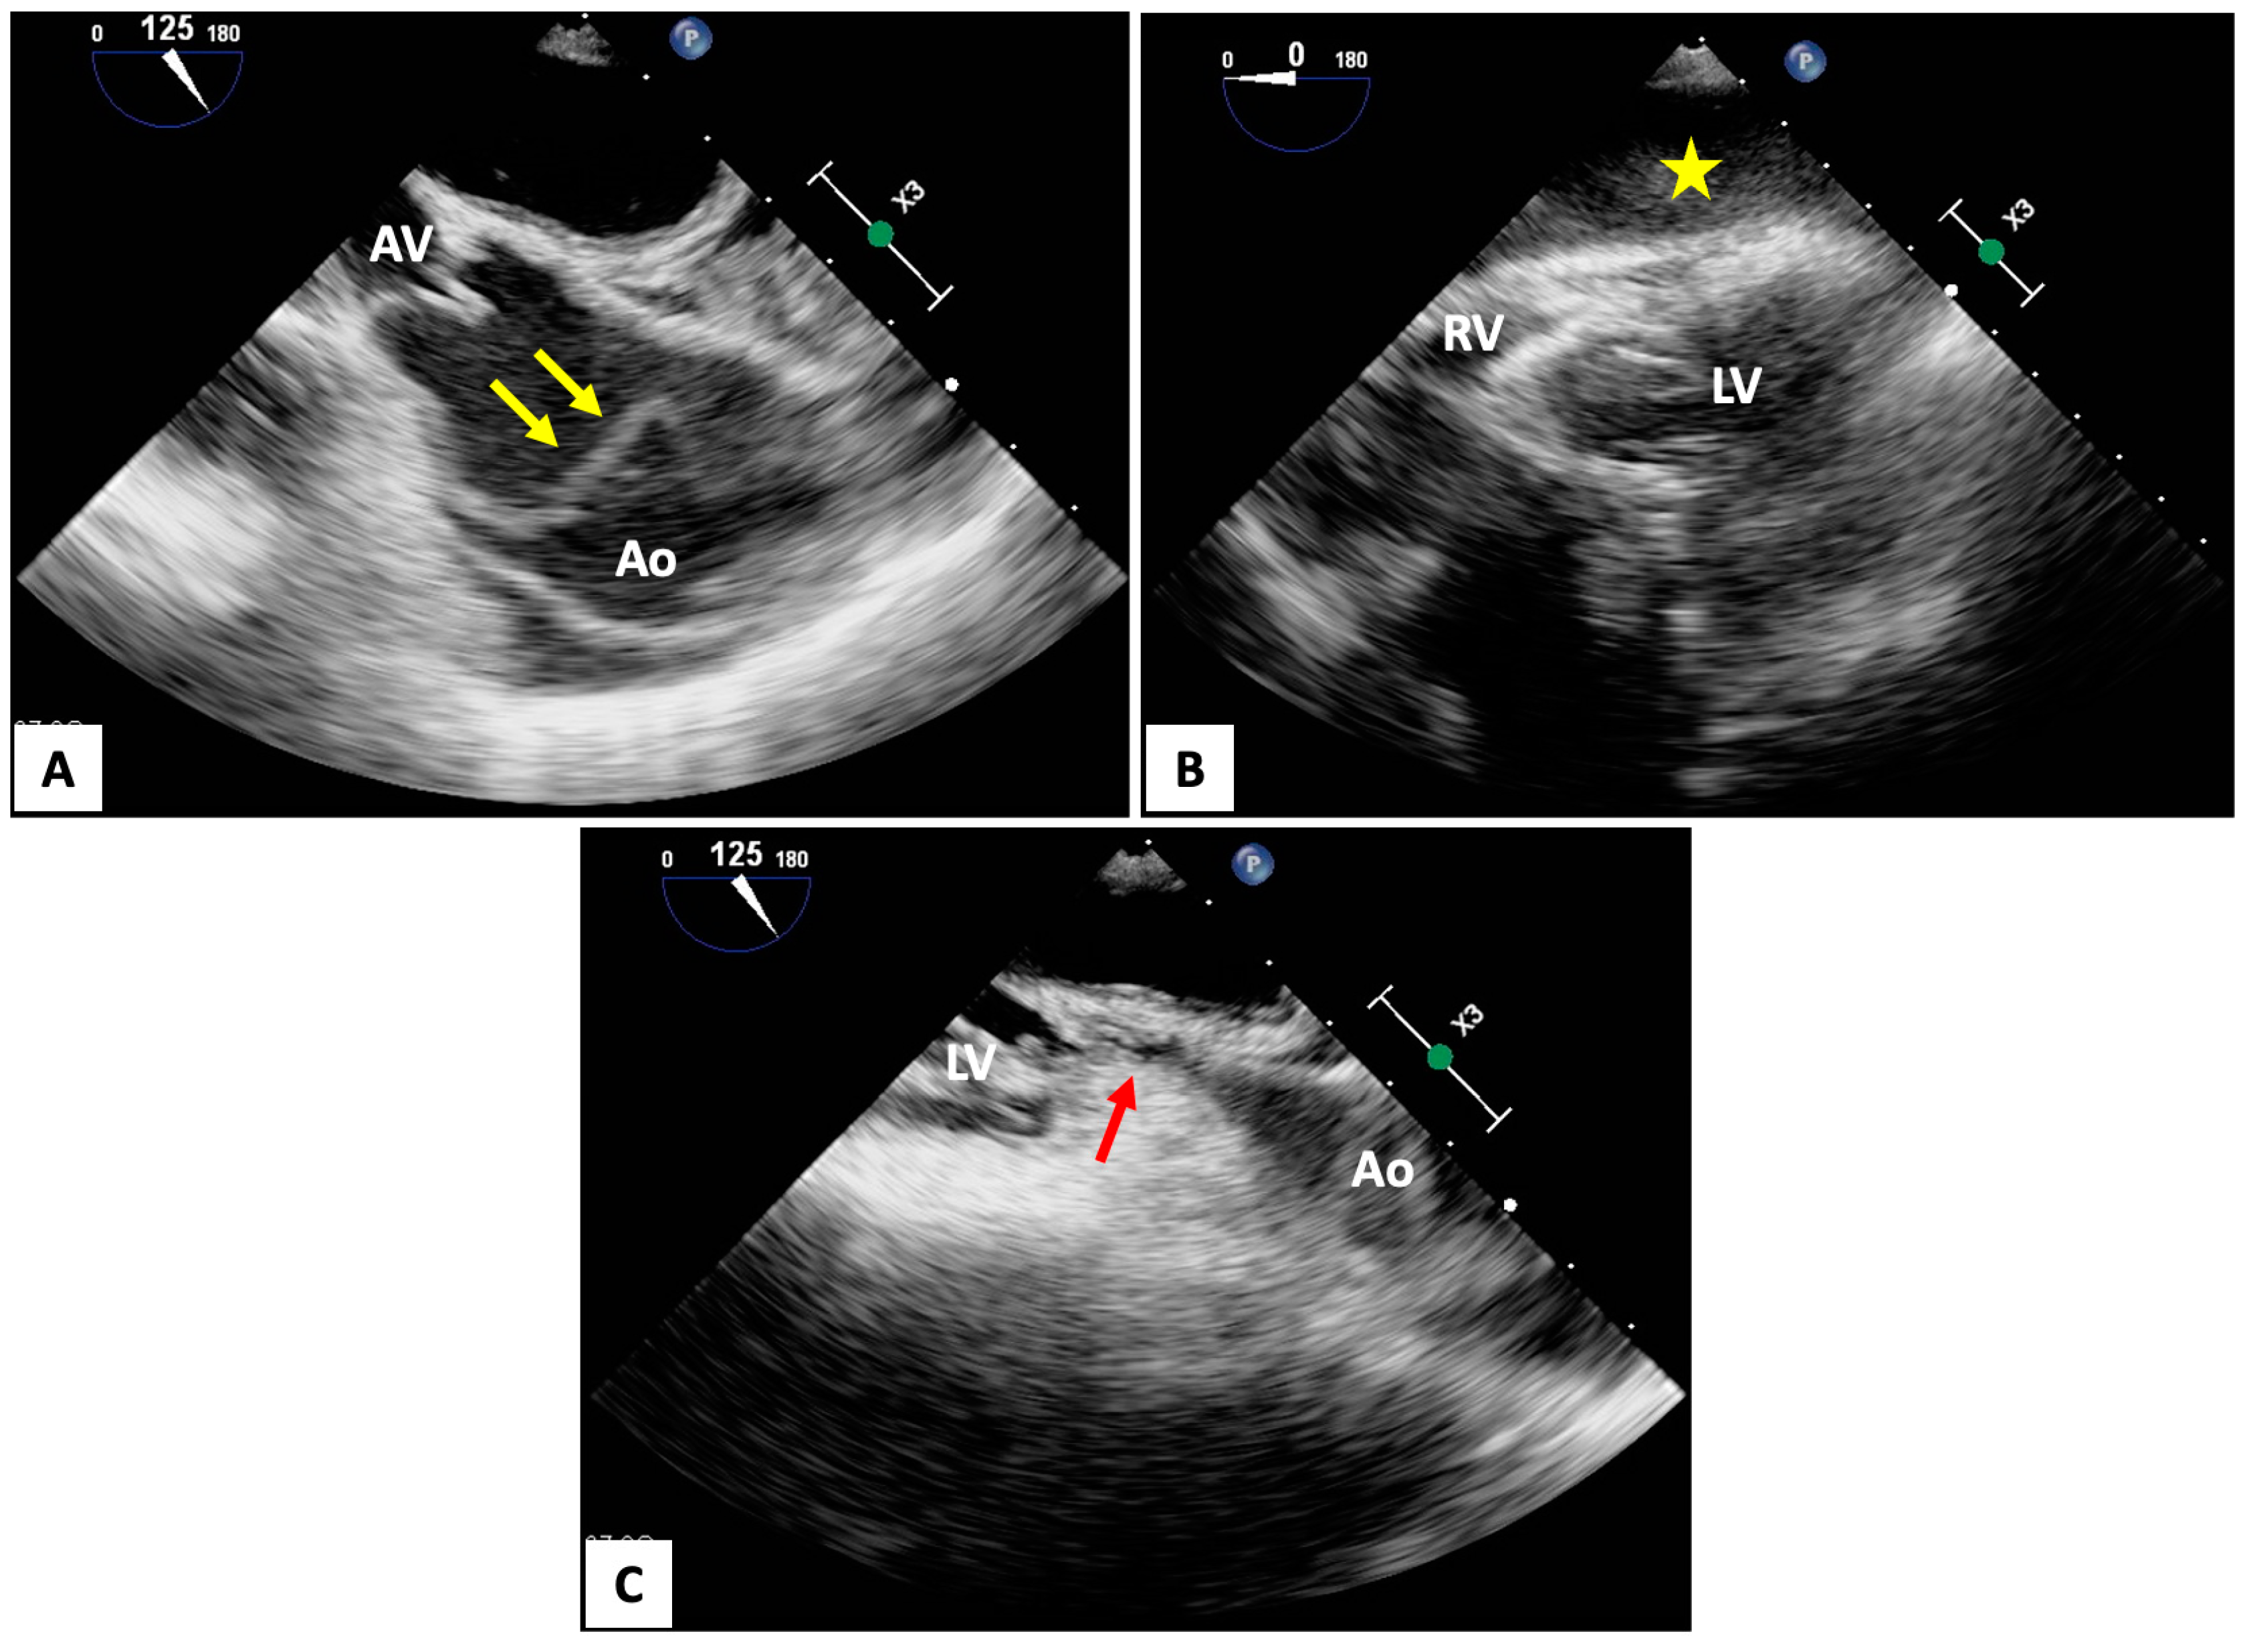

- Catena, E.; Ottolina, D.; Fossali, T.; Rech, R.; Borghi, B.; Perotti, A.; Ballone, E.; Bergomi, P.; Corona, A.; Castelli, A.; et al. Association between left ventricular outflow tract opening and successful resuscitation after cardiac arrest. Resuscitation 2019, 138, 8–14. [Google Scholar] [CrossRef] [PubMed]

- Teran, F.; Prats, M.I.; Nelson, B.P.; Kessler, R.; Blaivas, M.; Peberdy, M.A.; Shillcutt, S.K.; Arntfield, R.T.; Bahner, D. Focused Transesophageal Echocardiography During Cardiac Arrest Resuscitation: JACC Review Topic of the Week. J. Am. Coll. Cardiol. 2020, 76, 745–754. [Google Scholar] [CrossRef] [PubMed]

- Teran, F.; Owyang, C.G.; Martin-Flores, M.; Lao, D.; King, A.; Palasz, J.; Araos, J.D. Hemodynamic impact of chest compression location during cardiopulmonary resuscitation guided by transesophageal echocardiography. Crit. Care 2023, 27, 319. [Google Scholar] [CrossRef]